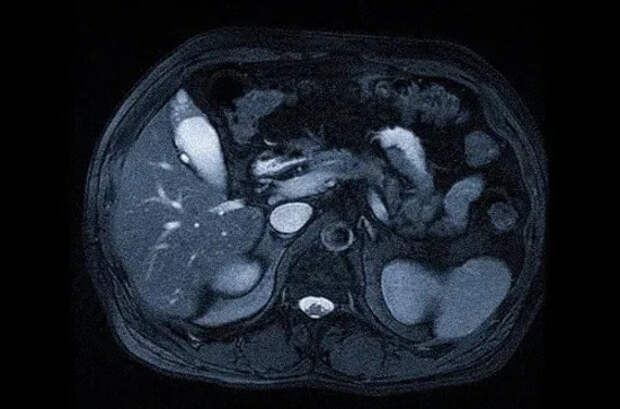

Ключевая часть протокола — многофазное сканирование, которое фиксирует, как контраст распространяется по сосудам и тканям печени:

- Артериальная фаза (20-35 секунд): Контраст заполняет печеночную артерию. Гиперваскуляризированные образования (ФНГ, аденома, гепатоцеллюлярный рак) активно накапливают контраст и ярко «вспыхивают».

- Портально-венозная фаза (60-70 секунд): Контраст заполняет воротную вену. Паренхима печени становится более однородной. В этой фазе хорошо видны гиповаскуляризированные метастазы.

- Отсроченная (равновесная) фаза (3-5 минут): Контраст распределяется между внутри- и внесосудистым пространством.

- Гепатобилиарная фаза (10-20 минут, для специфических контрастов): Контраст захватывается гепатоцитами и выделяется в желчные протоки. Нормальная ткань печени и некоторые образования (ФНГ) накапливают контраст, в то время как злокачественные опухоли (метастазы, холангиокарцинома) — нет, что делает их четко видимыми как «дефекты накопления».